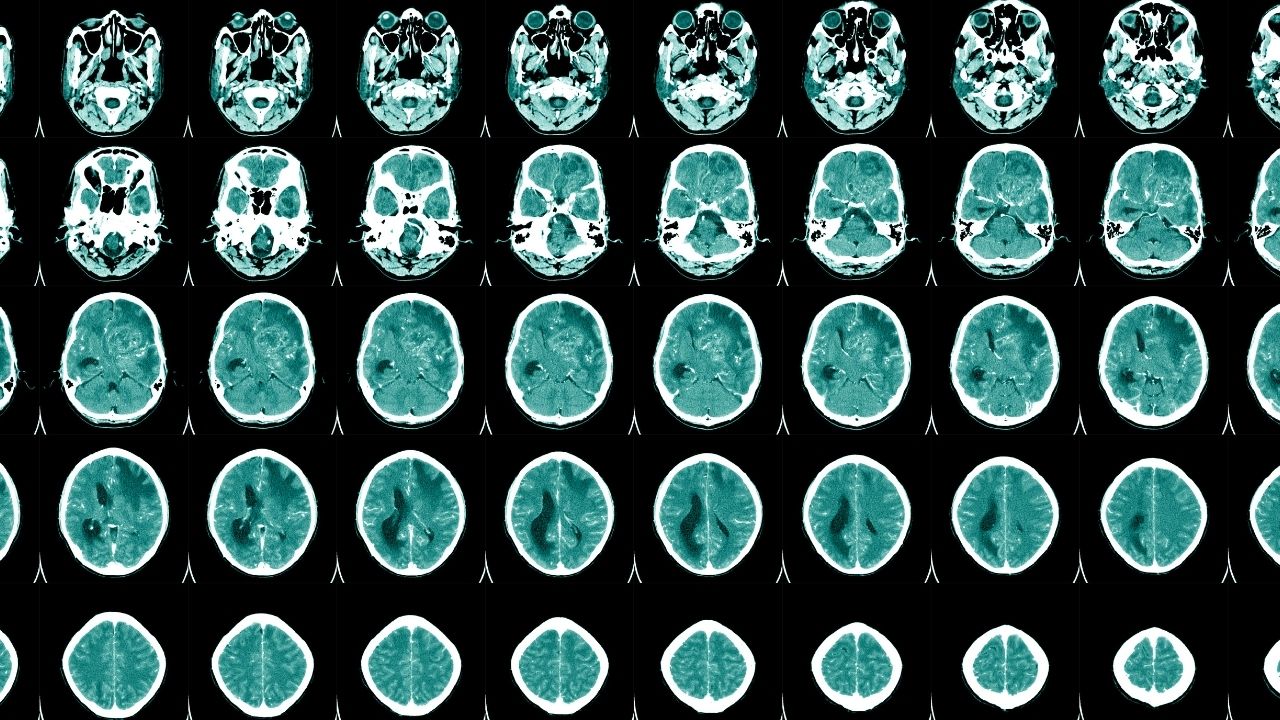

Tıbbi olarak menenjit, "meninks" adı verilen beyin ve omuriliği çevreleyen zarların iltihaplanması olarak tanımlanır. Bu iltihap, genellikle virüs, bakteri ya da nadiren mantar kaynaklı olabilir. En tehlikeli türü bakteriyel menenjittir ve acil tedavi gerektirir. Tedavi edilmediğinde sarılık, epilepsi, işitme kaybı ve bilişsel gelişim gerilikleri gibi kalıcı sağlık sorunlarına neden olabilir. Ancak her menenjit vakası bu komplikasyonlara yol açmaz. Hastalığın şiddeti, kaynağı ve erken teşhis bu süreçte belirleyici olur.